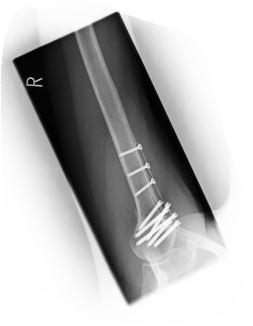

Hallo, ich hatte eine subkapitale Humerus Mehrfragmentfraktur rechts AO 11-A3. Gemacht wurde Rekonstruktion der Gelenkfläche, Aufrichten des Kopfes, Naht der Rotatorenmanschette und Stabilisierung mit winkelst. Platte 3 Loch. Die OP war vor 3 Wochen, bin in Physio und trainiere viel zu Hause. Die Ärzte sind mit der Beweglichkeit sehr zufrieden. Ich komme seitlich auf 90 Grad, ABER wenn ich den Arm nach vorne ausstrecke, kommt die Schulter mit nach vorne, bzw. oben. Insgesamt steht die betroffene Schulter weiter vorn. Bewegungen nach vorne kommen mir leicht blockiert vor und sehen auch komisch aus, weil die Schulter mit hoch kommt, ich mich aber auch bei größter Anstrengung nicht anders bewegen kann. Hängst das mit dem Supraspinatus zusammen? Wie lange muss ich mit diesem gestörten Bewegungsbild rechnen? Lösen sich OP-Fäden noch auf, die innerlich verwendet wurden? Vielen Dank für Antworten im voraus.

Vielen Dank für die Antwort. Mein Physio hat gestern mit mir Übungen begonnen zur Rotation. Ging sehr schwer, besonders die Aussenrotaion. Zu Hause habe ich einen Schulterstuhl, der nur für Ab/Aduktion eingestellt ist. Nun habe ich beim Chirurgen angerufen und dieser meinte, die Rotation soll erst 6 Wochen nach OP begonnen werden. Ein Muskel wurde über die Platte gelegt und an 2 Stellen befestigt, dies verursache, dass die Schulter nach vorne steht. Wie gesagt, zur Seite geht auf 90 Grad ohne Einschränkung oder Schmerz. Der Arm war nur 5 Tage vor OP ruhiggestellt und danach ging es gleich mit Physio los. Welche Muskeln sind für die Rotation zuständig? Liebe Grüße -

Hallo, nun bin ich in Woche 5 nach der Op angelangt und die Schulter bewegt sich noch immer stark mit nach oben, wenn ich den arm hebe. Das Schulterblatt hinten steht stärker raus und die Schulter steht noch immer weiter vorne. Dadurch ist das ganze Bewegungsbild gestört und es hat Auswirkungen auf den gesamten Rücken. Der Arzt, den ich gestern dazu befragte, meinte, es könne sein, dass die Platte oben ein Engpass macht, weil sie 3 mm dick sei (Carbofix) und dies so bleibe. bis man sie entferne. Dies sei ab dem 6 ten Monat möglich. Ich denke, dis dahin werde ich einen völlig verrenkten Rücken haben und es kommt zu falschen Bewegungsabläufen. Damit kann ich mir gar nicht vorstellen, arbeiten zu gehen usw. Welche Erfahrungen gibt es hierzu, kann ich erwarten, dass sich das noch bessert.? Röntgenbilder geibt es erst nächste Woche , um zu beurteilen, wie genau der Stand ist. Bin beunruhigt, denn der Stand heute kommt einer Behinderung gleich. Merci im Voraus! -